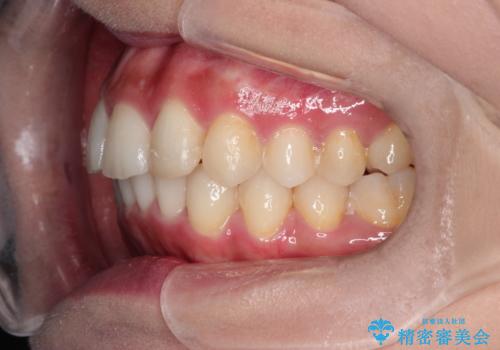

前歯のガタガタを目立たない装置でなおしたい インビザラインによる目立たない矯正

- 目立たない装置でガタガタをきれいにしたいとのご希望で来院されました。

インビザラインで矯正することとなりました。

左上の前から2番目の歯が通常とは異なる形態をしており、左右対称にすることはできませんでしたが、インビザラインで周りに気づかれることなく矯正治療をおえることができ、満足していただけました。